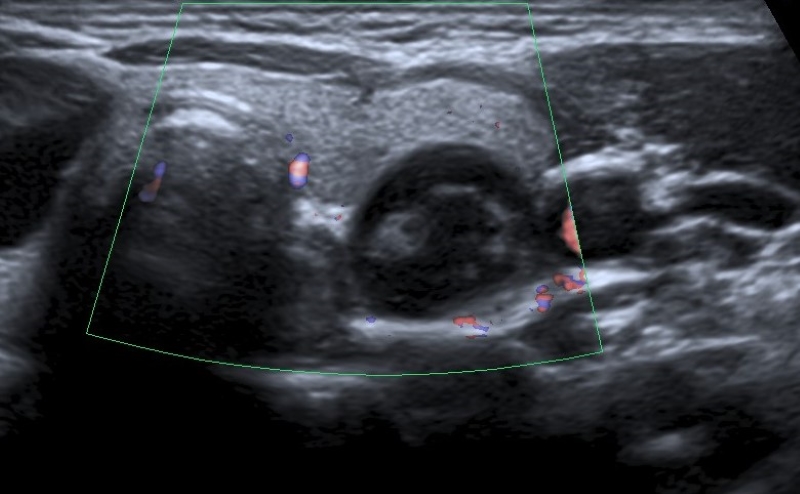

Vascularización

La vascularización se evalúa con la herramienta de Doppler color, y se debe determinar si esta se encuentra ausente (Fig. 18) o aumentada en el nódulo en relación con el parénquima tiroideo. La vascularización aumentada puede presentar dos patrones: central (Fig. 19) y periférico (Fig. 20), siendo el aumento de la vascularización central con disposición caótica la que presenta mayor riesgo de malignidad2,14,19,22,23,24. Un patrón vascular periférico se asocia mayormente con benignidad15,18, aunque algunos autores han calificado a la vascularización como una característica no significativa para diferenciar nódulos benignos de malignos2,3,14,16.